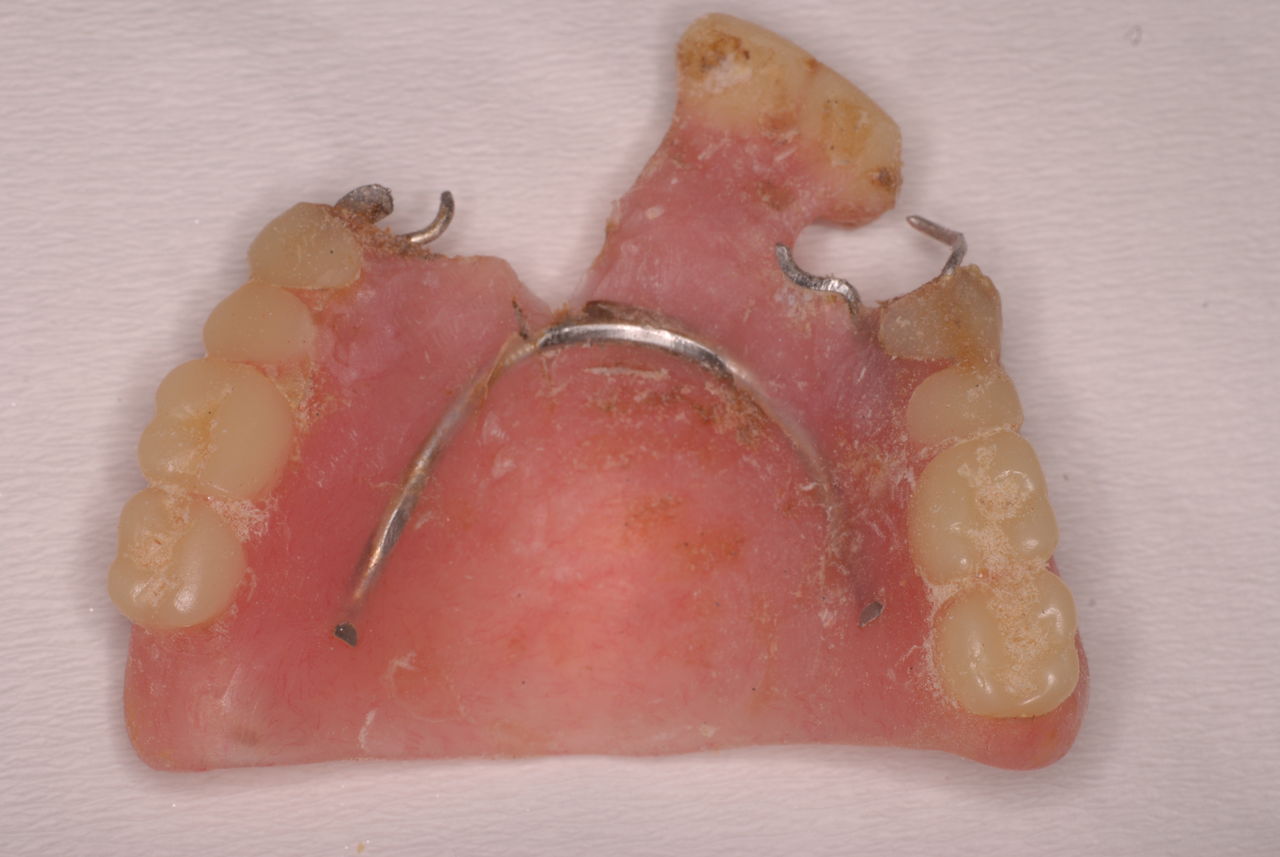

今回の方は、何十年にもわたりやすい保険の入れ歯で苦労したのです。それで自分で修理しながら使用していたという猛者でした。

所が、見た目も悪くこれでどうやって人と会っていたのか、食べていたのか皆目想像できない方でした。

カビか何かが入り込んでいる異様な入れ歯でした。

上の歯は一本がブラブラでしたね。

カビのような汚い部分を除去した直後です。